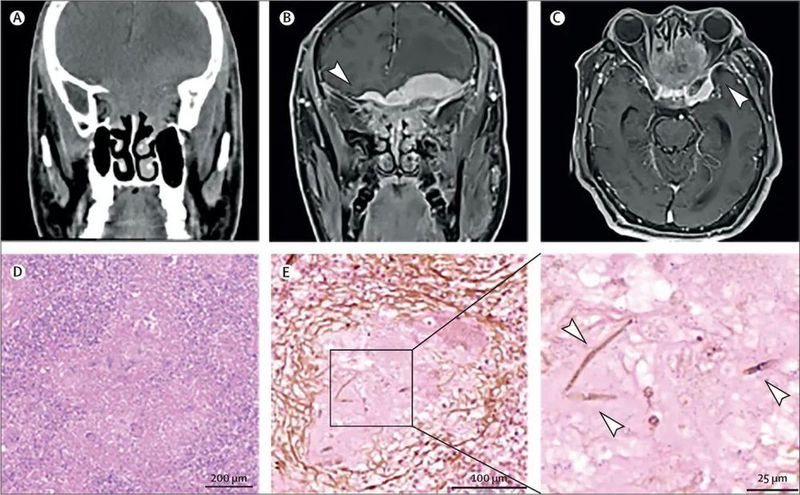

一名45岁男性患者,既往免疫功能正常,来自热带岛屿海南,主诉一过性四肢无力,并伴有轻度头痛持续4个月,除此之外无其他不适。患者有乙型肝炎及慢性肝硬化病史,其他情况无特殊。体格检查未见眼科、耳鼻喉科或神经系统阳性体征。头部CT显示病变累及鼻窦、眼眶及脑部(图A)。MRI显示前颅底轴外占位性病变,并具有典型的硬膜尾征(图B、C)。

(A) 头部CT显示鞍区的弥漫性病变,累及鼻腔、鼻窦和眼眶(冠状位)。T1加权增强头部MRI图像显示前颅底肿块,涉及鼻窦、眼眶和海绵窦,并可见典型的硬膜尾征(箭头所示;B为冠状位,C为轴位)。